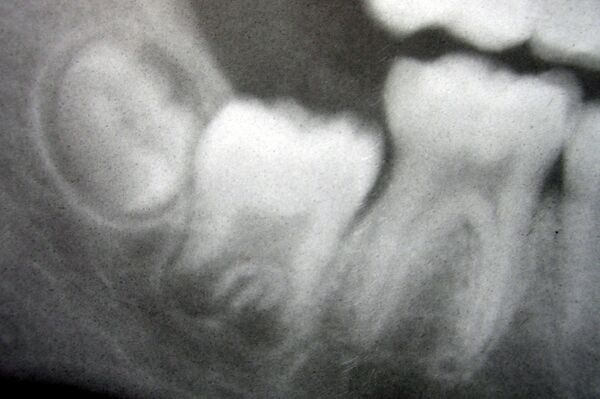

Зуб расположен в альвеолярном отростке верхней челюсти или в альвеолярной части нижней, состоит из ряда твёрдых тканей (такие, как зубная эмаль, дентин, зубной цемент) и мягких тканей (пульпа зуба).

Анатомически различают коронку зуба (выступающую над десной часть зуба), корень зуба (часть зуба, расположенная глубоко в альвеоле, покрытая десной) и шейку зуба — различают клиническую и анатомическую шейки: клиническая соответствует краю десны, а анатомическая является местом перехода эмали в цемент, что означает, что анатомическая шейка является фактическим местом перехода коронки в корень. Примечательно, что клиническая шейка с возрастом смещается в сторону верхушки корня (апекса) (так как с возрастом происходит атрофия десны), а анатомическая — в противоположную (так как с возрастом эмаль истончается, а в области шейки может полностью истираться в силу того, что в области шейки её толщина гораздо меньше). Внутри зуба располагается полость, которая состоит из так называемых пульповой камеры и корневого канала зуба.

Через специальное (апикальное) отверстие, расположенное в верхушке корня, в зуб идут артерии, которые доставляют все необходимые вещества, вены, лимфатические сосуды, обеспечивающие отток лишней жидкости и участвующие в механизмах местной защиты, а также нервы, осуществляющие иннервацию зуба.

Корни зубов, которые погружены в альвеолярные лунки верхней и нижней челюстей, укрыты периодонтом, который являет собой специализированную фиброзную соединительную ткань, которая удерживает зубы в альвеолах. Основу периодонту составляют периодонтальные связки (лигаменты), которые связывают цемент с костным матриксом альвеолы. С биохимической точки зрения, основу периодонтальных лигаментов составляет коллаген типа I с некоторым количеством коллагена типа III. В отличие от других связок тела человека, связочный аппарат, которые формирует периодонт, сильно васкуляризованный. Толщина периодонтальных связок, которая у взрослого человека составляет примерно 0,2 мм, уменьшается в пожилом и старческом возрасте.

Дентин — минерализованная, бесклеточная, бессосудистая ткань зуба, которая образует основную его массу и по строению принимает промежуточное положение между костной тканью и эмалью. Он твёрже кости и цемента, но в 4—5 раз мягче эмали. Зрелый дентин содержит 69 % неорганических веществ, 18 % органических и 13 % воды (что соответственно в 10 и в 5 раз больше, чем у эмали).

Дентин построен из минерализованного межклеточного вещества, пронзенной многочисленными дентиновыми каналами. Органический матрикс дентина составляет около 20 % общей массы и по составу близок к органическому матриксу костной ткани. Минеральную основу дентина составляют кристаллы апатитов, которые откладываются в виде зерен и шарообразных формирований — калькосферитов. Кристаллы откладываются между коллагеновыми фибриллами, на их поверхности и внутри самих фибрил.